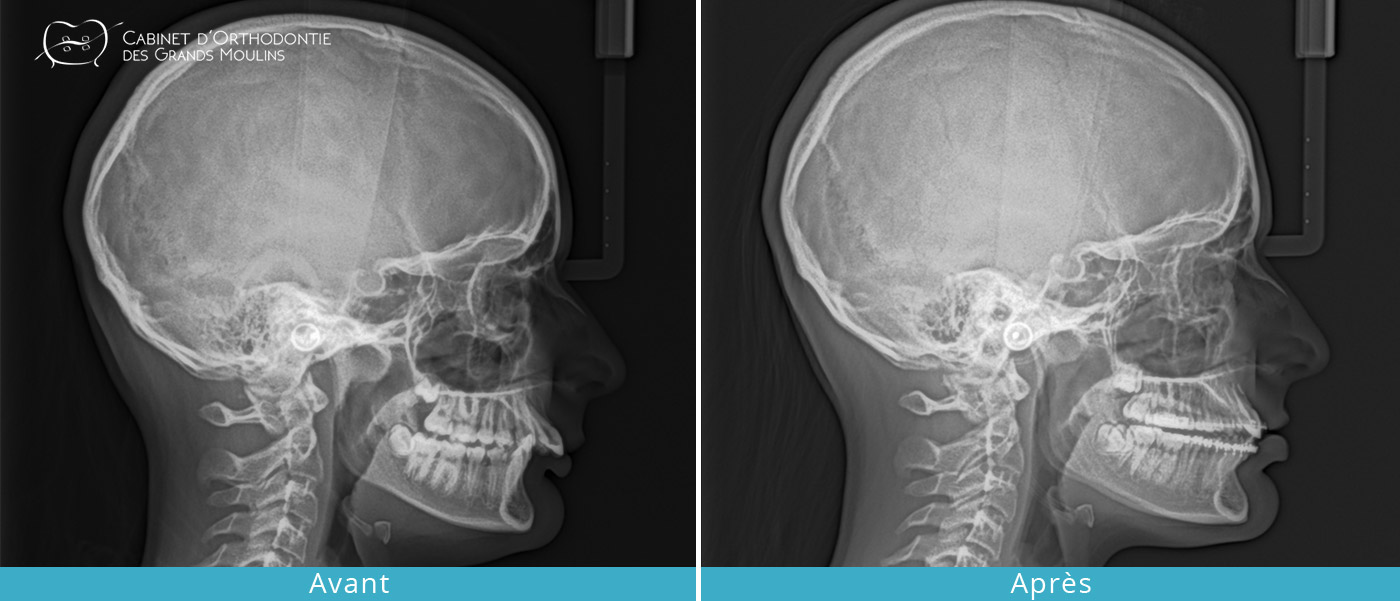

- Réduire les dysfonctions articulaires (craquements, douleurs, blocage, ) en améliorant l’occlusion dentaire et en corrigeant les décalages dentaires et squelettiques.

Ces traitements peuvent être complets, nécessitant parfois le recours aux extractions et/ou à la chirurgie maxillo-faciale ou partiels, dits « traitements de compromis ».

Dans certains cas et pour aider le traitement, des petites vis ou implants peuvent être mis en place afin d’avoir un ancrage solide pour déplacer les dents de façon plus efficace. Ces mini-vis ou mini-implants sont retirés à la fin du traitement et ne laissent aucune séquelle.